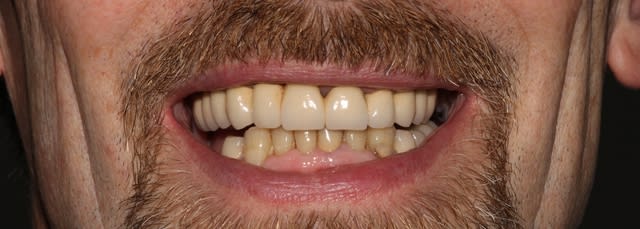

Là, on touche à la psychologie un peu particulière du patient: c'est pas franchement un bavard. Sympa, hein, mais réservé.Je n'ai jamais vraiment su ce qu'il pensait. (et vu l'excellent communicateur que je suis, faut avouer que les conversations tournaient vite court, 2 murs qui bavardent). Normalement, un mec chez qui tu tailles tout un maxillaire, il réagit. Là, rien, tout va bien. Du coup, l'esthétique lui allait tout à fait, mais je suis persuadé qu'une autre morpho aurait été parfaite également.

Seuls souhaits que j'ai réussi à en tirer/déduire: le moins de séances possibles, et des dents plutôt claires. Du coup, on est resté sur ce type de morpho, un peu par défaut, et on s'est concentré sur le fonctionnel.

Effectivement, mais peut-être aussi qu'il commençait à se détendre, et que les dents se voyaient plus car plus longues.

Ca se remarque, oui, et ça m'agace. C'est une de mes déceptions, avec le côté un peu trop blanc/ américain du résultat final. Je finis de poster demain pour l'autocritique finale.

Un de mes arguments pour ne pas retoucher la ligne des collets, c'était de ne pas aller perdre de la hauteur d'os ou chatouiller un terrain paro stabilisé. Ca, et éviter une séance supplémentaire.

(l'alignement des collets, par contre, ça va m'agacer pendant un bout de temps, je regrette de ne pas avoir pris le temps de le faire. Tant pis, ça n'aura pas d'incidence importante).

Dernier regret, je trouve les céramiques un peu trop "lisses", sans vie. Je sais que le patient voulait un sourire blanc, c'est bien normal, mais on aurait gagné à les caractériser un peu plus.